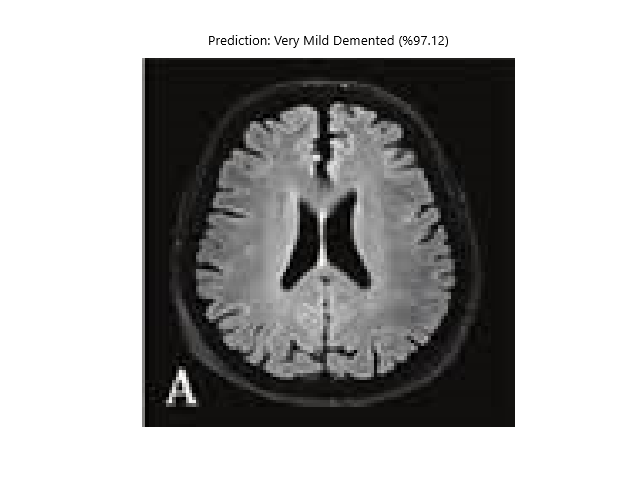

def show_image_with_prediction(image_path, prediction, confidence, class_names):

image = Image.open(image_path)

plt.imshow(image)

plt.title(f"Prediction: {class_names[prediction]} (%{confidence * 100:.2f})")

plt.axis('off')

plt.show()

test_image_path = 'MRI/or/fMRI/image/path'

prediction, confidence = predict(test_image_path, model, transform)

print(f'Prediction: {class_names[prediction]} (%{confidence * 100})')

show_image_with_prediction(test_image_path, prediction, confidence, class_names)Vbai Models;